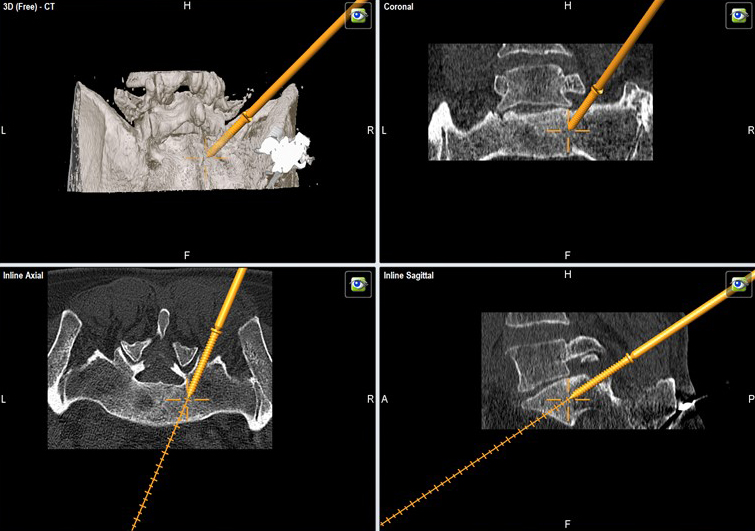

A 52-year-old male patient presented with low back pain and S1 radicular pain on the left side for 3 weeks. The laboratory tests of the blood showed enhanced inflammation signs. The MRI showed an infection of the L5/S1 disc (Fig 1). Indications for minimally invasive spondylodesis with intervertebral cage (Figs 2-6).